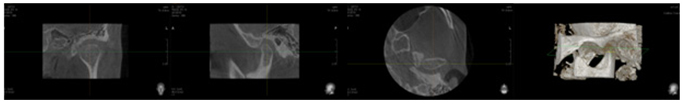

교정치료는 치열을 가지런하게 하면서 얼굴의 모습이 예쁘게 변화됨은 물론 기능까지 개선시키는 치료가 되어야 합니다. 기능 중에서는 씹는 기능이 굉장히 중요한데 씹는 기능의 출발점이 바로 턱관절입니다. 턱관절이 안정된 상태에서 치아들이 잘 맞물려야 제대로 된 기능을 발휘할 수 있습니다. 로스윌 교정치료는 단순한 치아이동이 아닌, 환자의 턱과 저작기능, 얼굴의 아름다움들이 모두 조화를 이루게 해 줄 뿐만 아니라 이렇게 얻어진 좋은 결과가 아주 오랫동안 지속되도록 해주는 치아교정 치료입니다. 이것을 다른 말로 표현한다면 기능과 아름다움을 동시에 이루어 주는 「Total Face Treatment의 개념」이라고 할 수 있습니다. 처음 진단과정에서부터 턱관절과 기능을 고려한 정밀진단 치료과정을 거쳐야 합니다. 로스윌 교정진단에는 일반적인 치아교정 치료과정에서 이루어지는 교정진단 외에 턱관절과 치아교합 상태를 정밀하게 확인하는 교합정밀진단과 턱관절 정밀 진단 치료과정이 포함되어 있습니다.

첫날 내원하시면 여러 가지 정밀검사를 시행합니다. 만약 턱관절에 문제가 있다면 바로 치아교정 치료를 시작하면 안 됩니다. 먼저 턱관절이 편안하고 안정된 상태가 되도록 턱관절을 안정시킨 다음, 그 상태에서 치아가 잘 맞물려서 제대로 기능을 할 수 있도록 교정치료를 진행해야 합니다. 정밀검사 결과 턱관절에 문제가 없다면 바로 치아교정 치료가 들어가며 얼굴의 심미성을 개선하고 가지런한 치열로 기능을 잘 할 수 있도록 교정치료를 진행합니다. <로스윌 준치과 교정치료 개념>